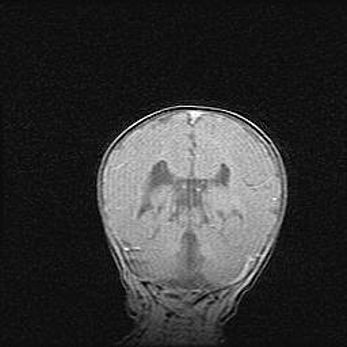

Мальформация Денди-Уокера. Киста задней черепной ямки.

Агенезия мозолистого тела.

Возраст: 2,5 месяца

Вес: 2420 г

Пол: женский

Окружность головы: 37 см

Срок гестации: 32 недели

Мальформация Денди—Уокера — редкий вид патологии ЦНС, представляющий собой врожденный порок развития каудального отдела ствола и червя мозжечка, ведущий к неполному раскрытию срединной (Мажанди) и латеральных (Лушка) апертур IV желудочка мозга. Для этогно синдрома характерна триада симптомов: гипотрофия червя мозжечка и/или полушарий мозжечка, кисты задней черепной ямки, гидроцефалия различной степени. В 70% случаев порок сочетается и с другими аномалиями головного мозга, в частности с агенезией мозолистого тела.